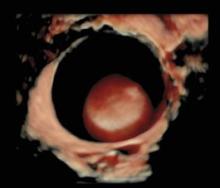

In seguito a questo grande impegno che sta continuando con il reclutamento di nuovi centri e di nuovi casi, ormai vi è in letteratura una forte evidenza che la valutazione soggettiva di una massa ovarica effettuata da un operatore dedicato attraverso l'ecografia sia un ottimo metodo per discriminare tra benignità e malignità ed in molti casi può essere suggerita pure una corretta diagnosi di natura della neoplasia sulla base della sola ecografia che, se associati alla clinica, all'esecuzione dei marcatori ovarici, aumentano ulteriormente la sensibilità nella diagnosi e nella stadiazione preoperatoria.

I progetti in essere prevedono l'esecuzione di ecografie ginecologiche di II livello di un operatore dedicato, atte a discriminare tra patologia benigna e maligna ovarica secondo la caratterizzazione della massa con i dati dello IOTA.

L’expertise dell’operatore, associato all’acquisizione da parte dell’Istituto di un’apparecchiatura di alto livello, dotata di software di ultima generazione anche con 3D e 4D, permettono di caratterizzare nei minimi dettagli l’eventuale presenza di patologia ovarica e di verificare l’eventuale disseminazione limitrofa agli organi circostanti. Questo da una parte dovrebbe permettere di evitare di misconoscere o sottovalutare alcune patologie ovariche potenzialmente evolutive in senso maligno e pertanto da indirizzare a trattamento chirurgico, e dall'altra di condurre un follow-up ecografico ad alcune patologie ovariche definite benigne secondo criteri standardizzati e ampiamente validati atti ad evitare una chirurgia non necessaria. Nel gruppo di lavoro IOTA infatti si è visto in questi anni che quasi l'80 percento delle masse ovariche operate risultavano benigne. E’noto che ogni procedura chirurgica è associata a possibili complicanze a breve come a lungo termine.